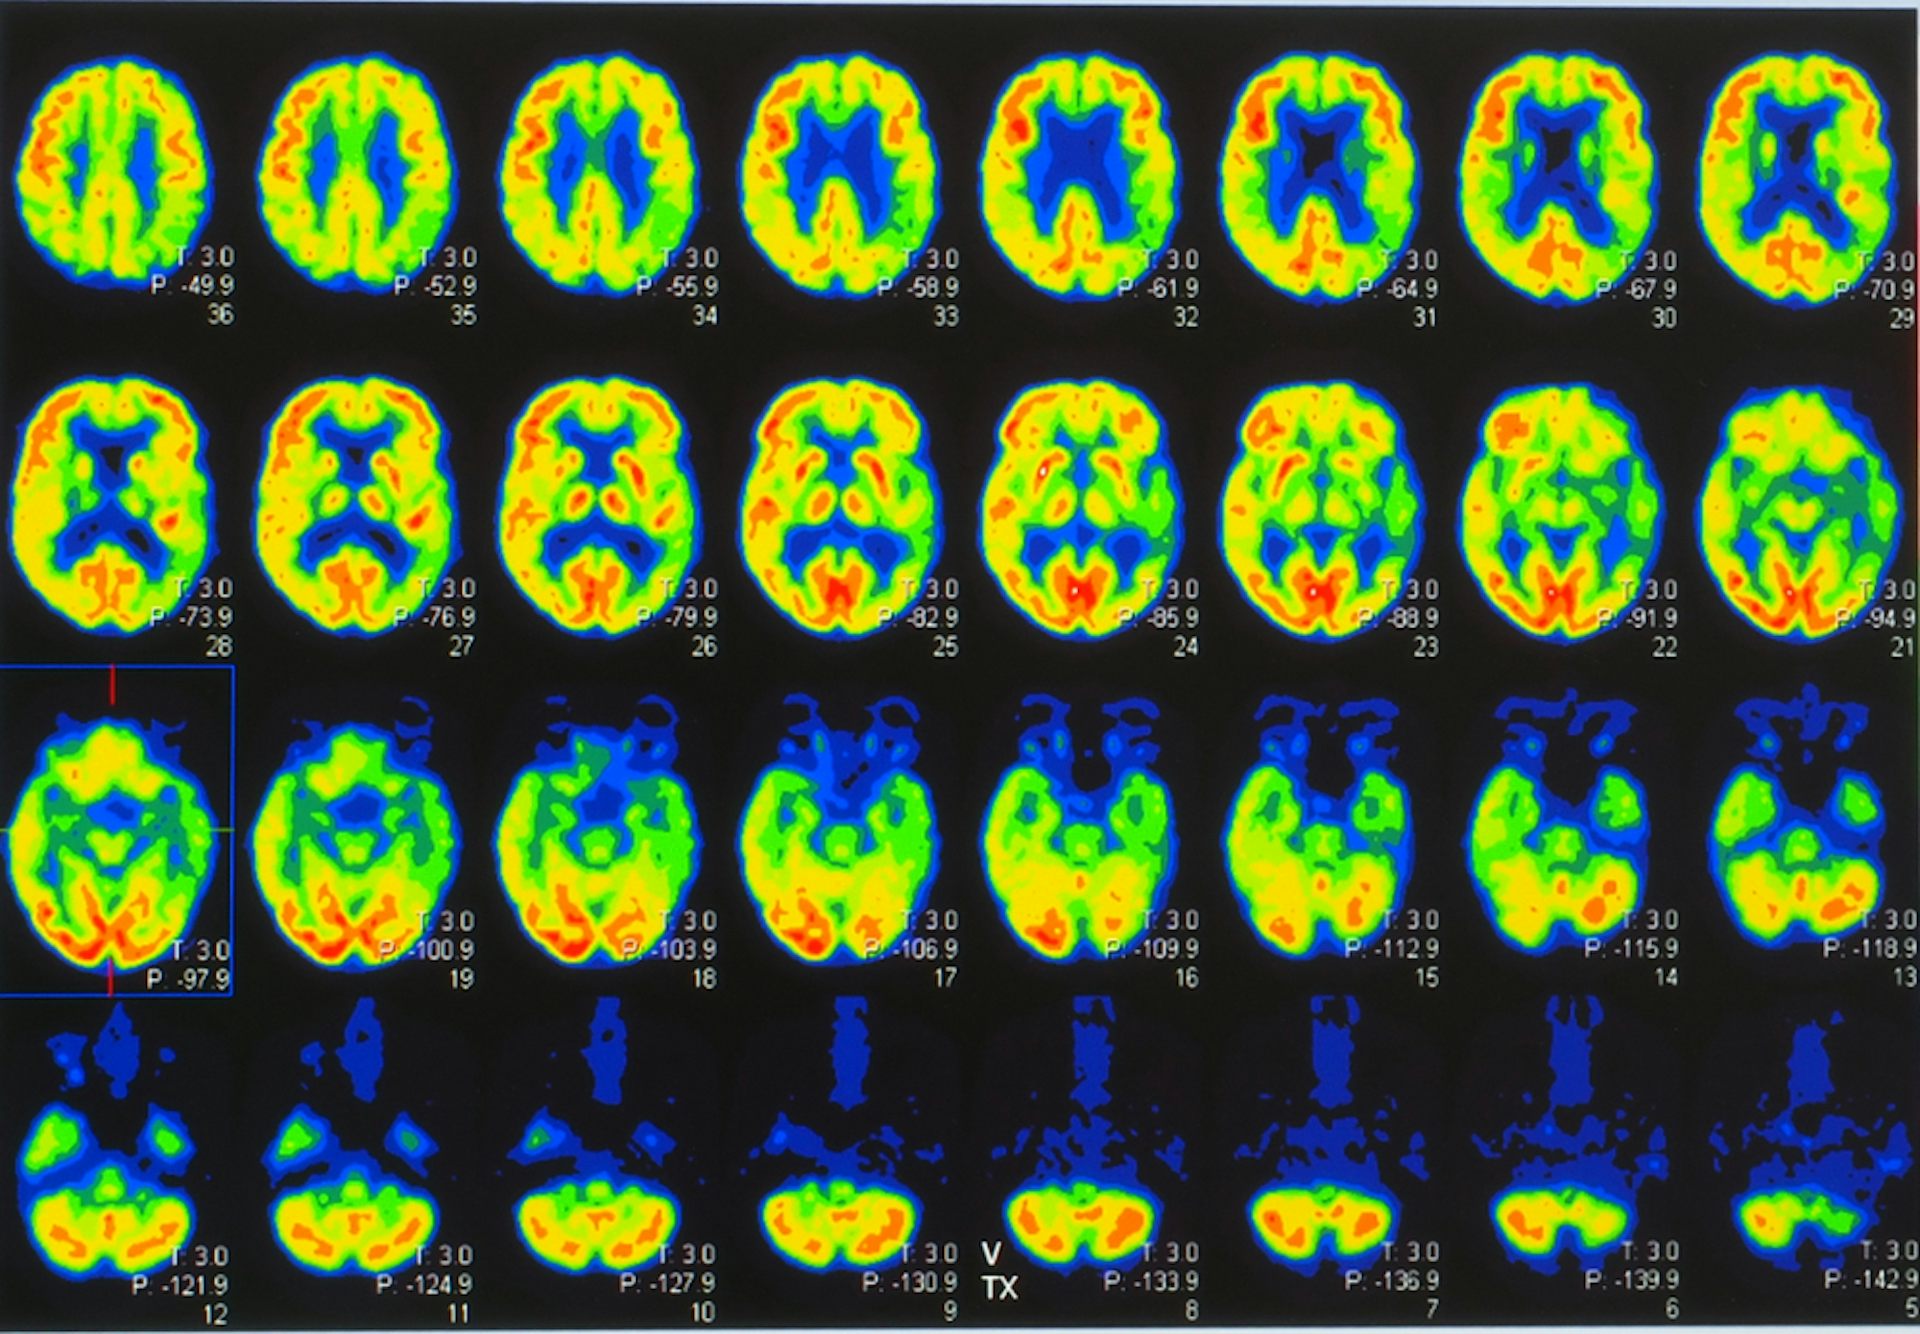

New Brain Imaging Study Reveals Signs Of Parkinson S Decades Before Symptoms Appear